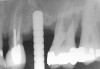

Accidental Penetration of Sinus Membrane with First Twist Drill

When using a 2-mm twist drill, the sinus could inadvertently be entered. This incursion can be verified by occluding the patient's nostrils and having the patient blow (Valsalva maneuver). If the membrane has been perforated, air bubbles will appear in the osteotomy. Some clinicans indicate that if a perforation has occurred, the sinus floor elevation procedure should be aborted and the site should be allowed to heal for 4 weeks and then redone.4 However, the situation may be salvageable (Figure 12, Figure 13, Figure 14, Figure 15). The amount of bone that is subantral can be re-evaluated, and then the second drill (eg, 2.8-mm wide) used, making sure not to enter the sinus. Similarly, the third drill (3.5-mm wide) can be used to proceed 1 mm short of the sinus floor. The initial sequence should be followed with respect to adding bone; whether or not a dome has formed should be verified radiographically. If the graft material is contained, then the procedure can be brought to conclusion as if a perforation had not occurred. On the other hand, if the material was not contained, it may appear on the radiograph as a "trail of smoke." In this case the procedure needs to be aborted or a lateral wall sinus lift needs to be performed to complete the task and repair the perforated membrane. In general, the ostium is 2.4-mm wide;33 it ranges from 2.14 mm to 6.77 mm.34 Therefore, particles that have escaped through the membrane will probably be swept through the ostium by the ciliated columnar epithelium without any untoward occurrence. Other authors have also noted that a perforation of the membrane does not necessarily result in failure of an implant that penetrates into the sinus.35

Figure 12  Initial radiograph at site No. 3.

Figure 12

Figure 13  Despite initial perforation into the sinus with the 2.1-mm twist drill, the drilling sequence was continued after the drill depth was adjusted to be 1 mm short of the subantral floor. The radiograph demonstrates that after the subantral floor was up-fractured and bone was added via the osteotomy, the initial puff of bone was contained. Therefore, the procedure could continue.

Figure 13

Figure 14  Additional bone was added via the osteotomy.

Figure 14

Figure 15  Implant successfully placed.

Figure 15